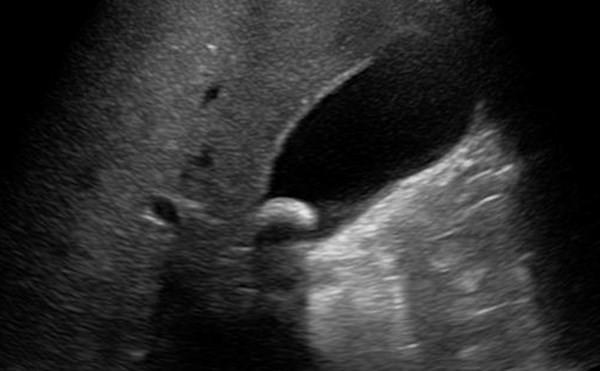

Gallbladder